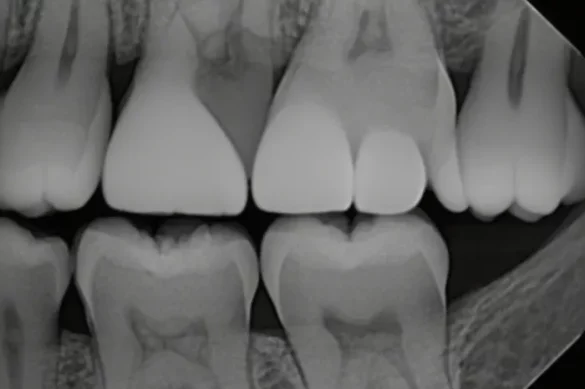

A bitewing photograph is a unique form of dental X-ray designed to expose info of the top and decrease returned tooth in a single area—typically the premolars and molars. The name “bitewing” comes from the wing-fashioned tool the affected person bites directly to keep the X-ray movie or sensor in place. The movie is placed in order that the X-ray will seize each the crowns of the top and decrease tooth and the bone among them.

Bitewing pictures display the crowns of each top and decrease enamel in a specific section, plus the peak of the bone among those enamel. The root suggestions and surrounding jawbone aren’t completely seen in bitewing pictures.

Periapical pictures display the whole tooth—from the crown right all the way down to the end of the foundation—and the bone shape across the root. These pictures aren’t as correct at shooting the touch region among adjoining crowns as bitewings are.

Bitewing pictures are exceptional for detecting cavities among enamel and tracking bone stages that is probably stricken by gum disease. Periapical pictures excel at highlighting issues that arise at the foundation or beneath the gum line, including abscesses, cysts, or intense bone loss.

To take a bitewing photograph, the X-ray beam is placed at a particularly low vertical angulation (normally around +five stages). This angulation lets in for a clean view of the crown margins and call factors among adjoining enamel. Bitewings hold those edges separate, supporting dentists test for cavities and compare the match of fillings or crowns.

In contrast, periapical pictures normally require a extra vertical angulation (from +10 to +30 stages for top enamel) to seize the foundation suggestions. However, this better attitude can purpose the seen a part of the crown to overlap with the foundation, from time to time making it tough to peer the crown margin clearly. That method periapical X-rays aren’t the exceptional desire for locating cavities on the crown facet or for checking the bone stage simply beneath the crown.